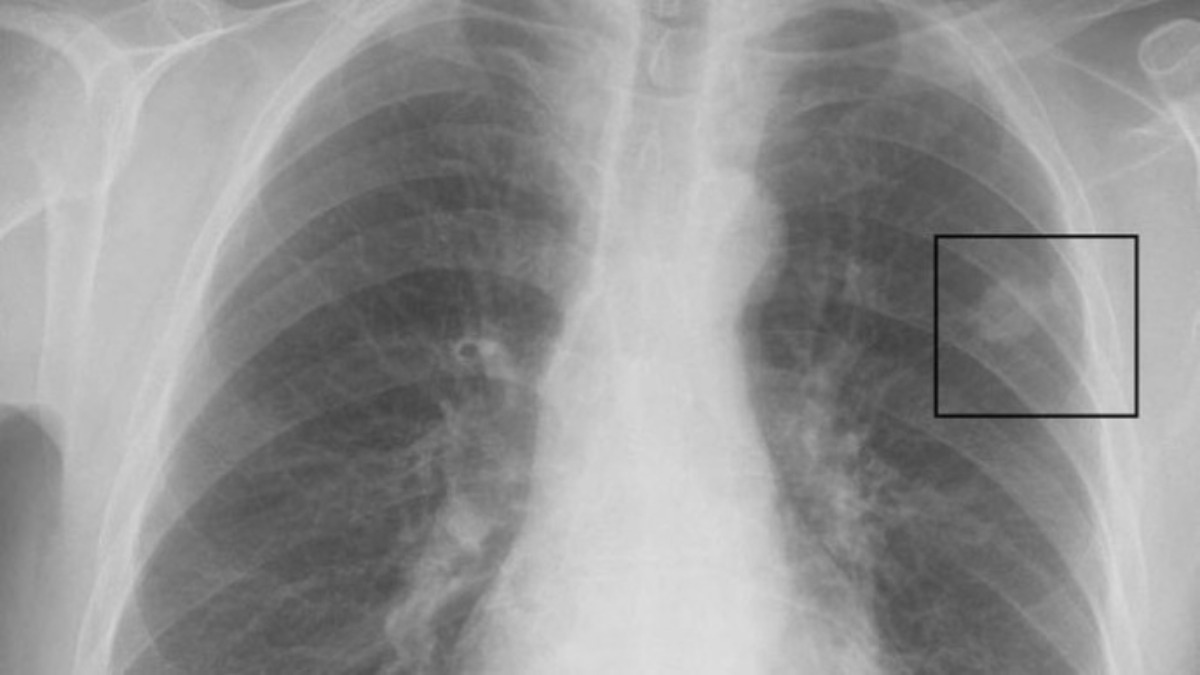

Pošto se kovid infekcija javlja direktno i indirektno u nekoliko organa, uključujući pluća, mozak i bubrege, istraživači vjeruju da matične ćelije raka, takođe, mogu da se razviju u više organa. Matične ćelije su nediferencirane ćelije koje imaju sposobnost da se razviju u mnogo različitih tipova ćelija u tijelu.